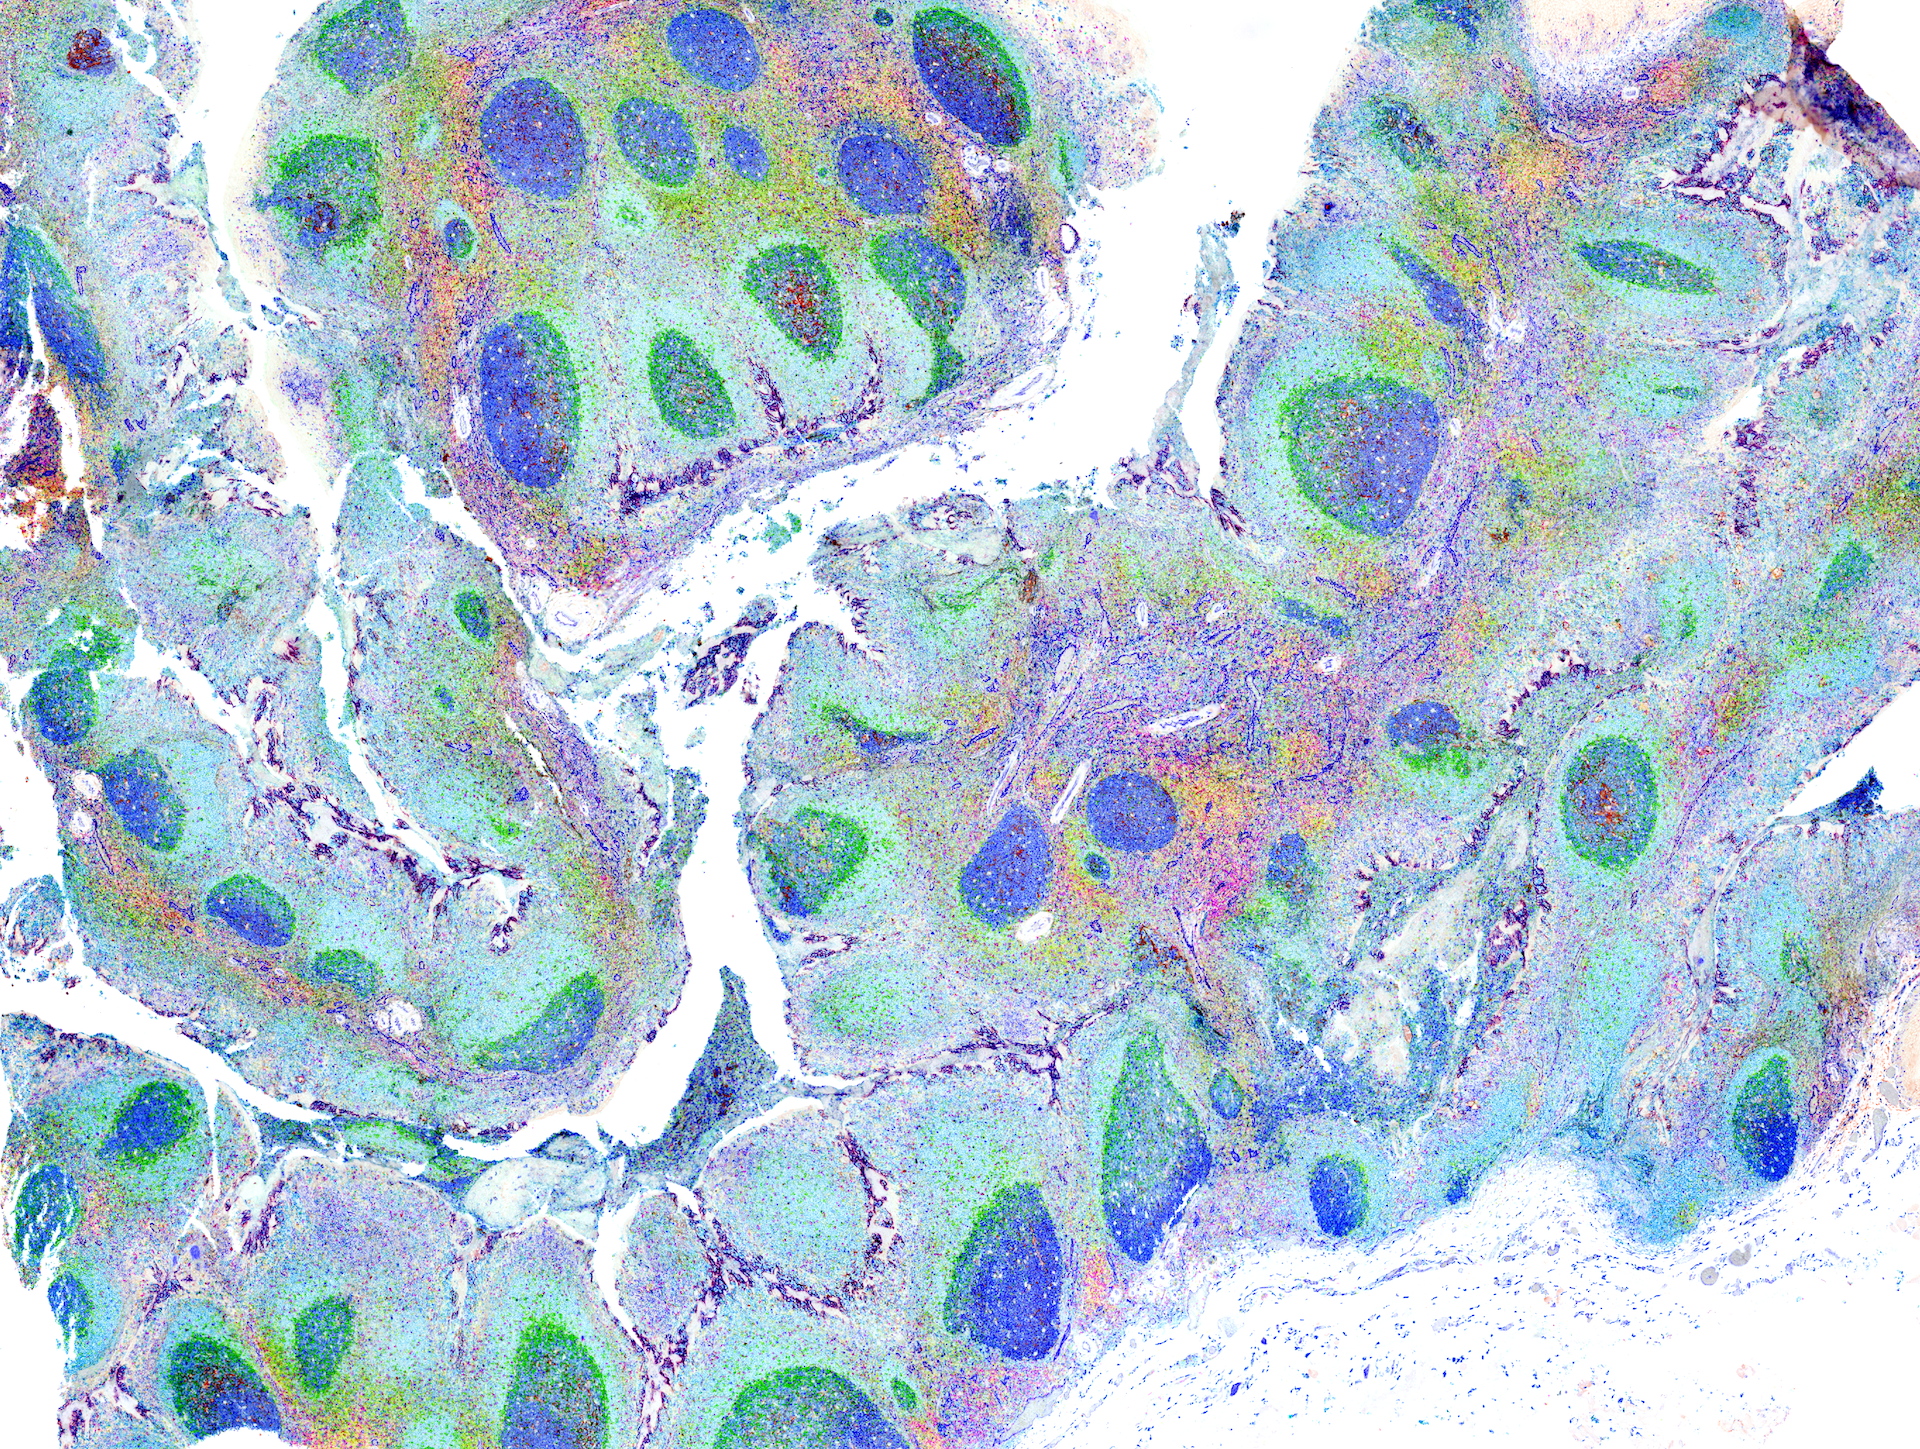

Revealing the hidden beauty of immune cells, these stunning microscopy images bring to life the intricate world of immune cells. The images dispatch us through the lens of a powerful microscope into real tissue structures, where we land amidst immune cells at work. Each colorful panorama is the product of researchers delicately staining a tissue sample and then digitally altering the visuals to differentiate between the tissue structures and immune cells.

Here, you’ll witness how researchers at La Jolla Institute for Immunology explore the secrets of the immune system, one microscopic detail at a time—in real time. Thanks to a generous gift from Michael and Ellise Coit, our Microscopy and Histology Core Facilities acquired an advanced multiplex imaging technology, enabling LJI scientists to study the immune system’s response to cancers, autoimmune diseases, and infectious diseases.